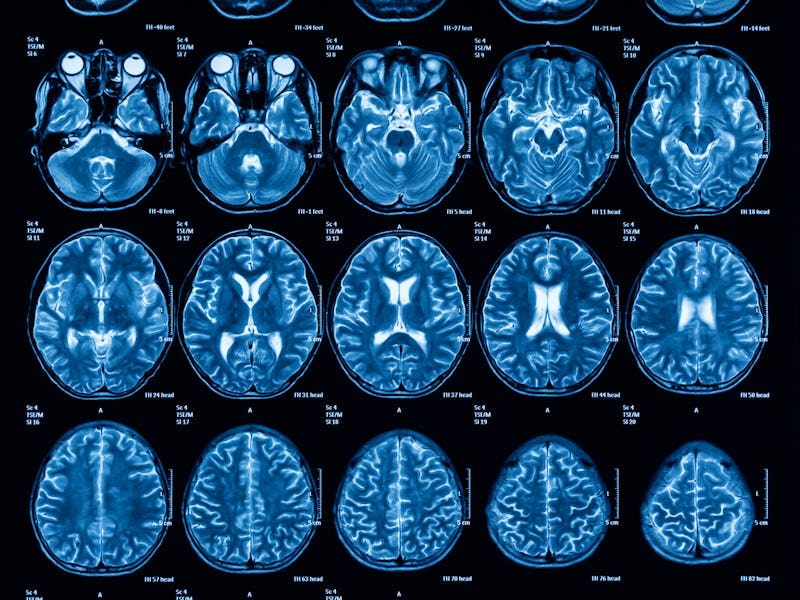

Into the brain — Blindsight results from damage to an area of the brain called the primary visual cortex. This is one of the areas, as you might have guessed, responsible for vision. Damage to the primary visual cortex can result in blindness – sometimes total, sometimes partial.

So how does blindsight work? The eyes receive light and convert it into information that is then passed into the brain. This information then travels through a series of pathways through the brain to eventually end up at the primary visual cortex. For people with blindsight, this area is damaged and cannot properly process the information, so the information never makes it to conscious awareness. But the information is still processed by other areas of the visual system that are intact, enabling people with blindsight to carry out the kind of tasks that we see in the case of Barry and Rick.

The visual cortex.